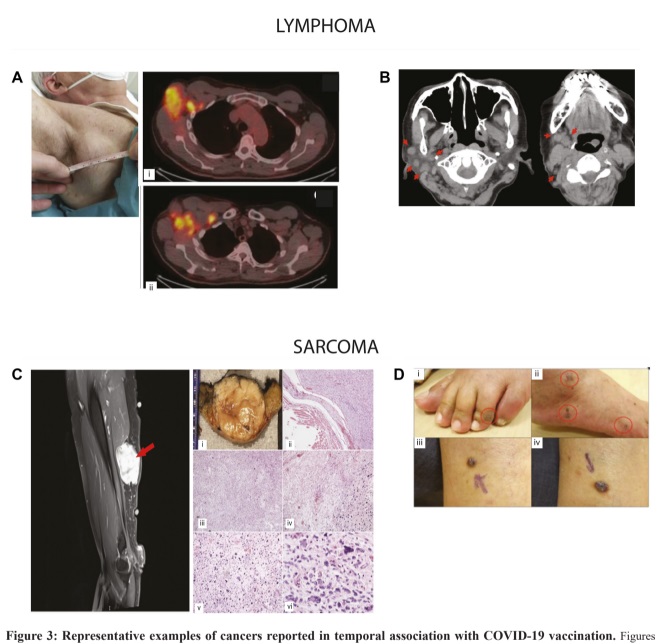

In het wetenschappelijke tijdschrift Oncotarget is recent een uitgebreide literatuurstudie verschenen waarin de link wordt onderzocht tussen COVID-19-vaccinatie en het ontstaan of gedrag van kanker. De studie is uitgevoerd door professor Charlotte Kupperwasser van de Tufts School of Medicine en arts-onderzoeker Wafik El-Deiry. De auteurs presenteren geen definitieve conclusies over oorzaak en gevolg, maar brengen bestaande wetenschappelijke signalen systematisch in kaart en bespreken hun mogelijke biologische betekenis.

Aanleiding voor het onderzoek is het groeiende aantal peer-reviewed publicaties sinds 2020 waarin diverse vormen van kanker worden beschreven die in samenhang optreden met COVID-19-vaccinatie. Om de aard en reikwijdte van deze waarnemingen te beoordelen, voerden de onderzoekers een systematische literatuurstudie uit over de periode tot oktober 2025.

In totaal werden 69 publicaties geïncludeerd. Het merendeel daarvan bestaat uit 66 casusbeschrijvingen, waarin samen 333 patiënten uit 27 landen worden besproken. Daarnaast analyseerden de auteurs twee retrospectieve populatiestudies – één uit Italië met ongeveer 300.000 deelnemers en één uit Zuid-Korea met circa 8,4 miljoen personen – waarin kankerincidentie en sterfte onder gevaccineerde populaties werden onderzocht. Ook werd een longitudinale studie meegenomen onder ongeveer 1,3 miljoen Amerikaanse militairen, die de periode vóór en na de pandemie beslaat.

De beschreven kankertypen zijn divers. Het gaat onder meer om hematologische maligniteiten, zoals non-Hodgkinlymfomen, cutane lymfomen en leukemie, maar ook om solide tumoren, waaronder borst-, long-, pancreas- en huidkanker, sarcomen en glioblastomen. Over de verschillende publicaties heen signaleren de auteurs enkele terugkerende klinische patronen, waaronder een opvallend snelle tumorprogressie en herhaling of heractivatie van eerder stabiele ziektebeelden. Ook worden atypische histopathologische kenmerken genoemd, zoals afwijkingen nabij vaccinatieplaatsen of regionale lymfeklieren.

Een belangrijk deel van de studie is gewijd aan mogelijke biologische mechanismen. De auteurs beschrijven dat COVID-19-vaccinatie ingrijpt op overlappende immuunroutes, zoals activatie van het aangeboren immuunsysteem, sterke interferon- en cytokineresponsen, oxidatieve stress en tijdelijke verstoring van immuuncel-homeostase. In theorie zouden dergelijke processen de groei van reeds bestaande gemuteerde celklonen kunnen bevorderen of veranderingen in de tumoromgeving kunnen veroorzaken die tumorgroei mogelijk maken.

De auteurs maken onderscheid tussen infectie en vaccinatie. Vaccinatie, zo stellen zij, kent unieke kenmerken, zoals de wijdverspreide biodistributie van genetisch gemodificeerd nucleïnezuur, de intracellulaire opname daarvan en mogelijk langdurige spike-eiwitexpressie in verschillende weefsels. Deze factoren zouden, indien bevestigd, invloed kunnen hebben op chronische immuunontregeling of de versnelling van groei van reeds aanwezige kwaadaardige cellen.

Om beter onderscheid te kunnen maken tussen tumoren die mogelijk samenhangen met infectie, vaccinatie of geheel onafhankelijke oorzaken, stellen Kupperwasser en El-Deiry een gestandaardiseerd pathologisch beoordelingskader voor. Een uniforme aanpak maakt het mogelijk om casussen internationaal te vergelijken en patronen systematischer te analyseren, schrijft het tweetal.

De studie besluit met een pleidooi voor transparante wetenschappelijke discussie, verbeterde surveillance en een geïntegreerde onderzoeksaanpak.